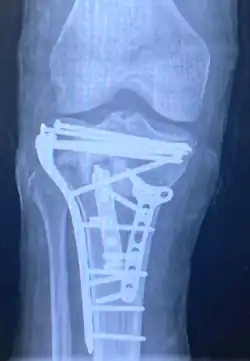

![]() | |

| A severe tibial plateau fracture with an associated fibular head fracture | |

A tibial plateau fracture requires orthopaedic surgical intervention for treatment. After X-ray and CT scans confirm fracture, Open Reduction Internal Fixation (ORIF) with medial and/or lateral plateau fixation is done. There are 5 different approaches that are most commonly used.[3]